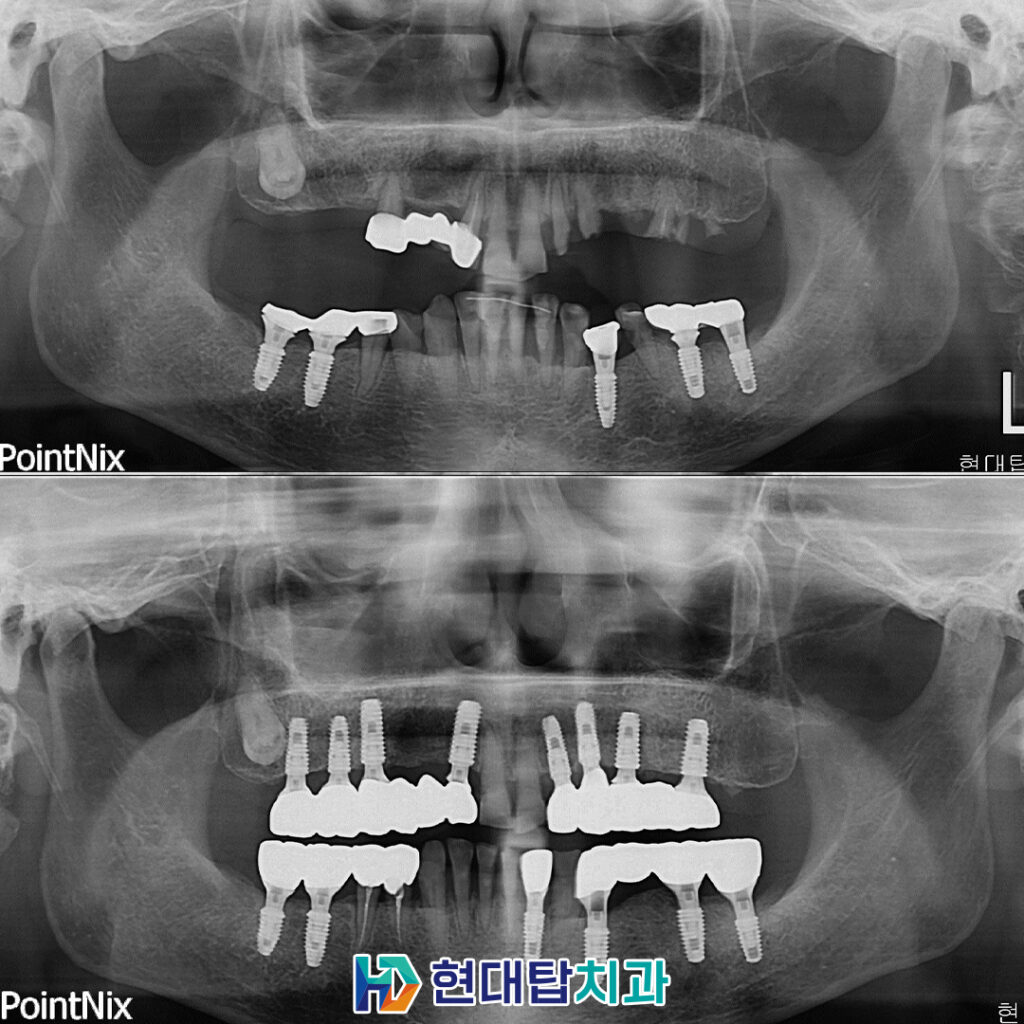

위 환자분은 52년생의 여성분으로

타원에서 진행하신 임플란트와 틀니를

사용 중이셨는데 틀니를 지지해 주던

치아가 파절되어 내원해 주셨습니다.

기존의 틀니를 사용하실 때부터

불편함이 많이 있으셨다고 하셔서

양쪽 위 8개의 임플란트를 식립하여

11개의 치아를 연결하는 브릿지의 형식으로

진행하기로 하셨고, 상태가 좋지 않던 오른쪽 아래

작은 어금니들은 신경치료 후 보철을 진행하였습니다.

또한 기존의 타원 임플란트 들의 보철물을

식립 예정인 임플란트와 교합이 잘 맞을 수 있도록

교체하도록 설명드렸고 치료 계획 수립하였습니다.

술후 파노라마입니다.

치아의 갯수가 많이 없다 보니

전체적으로 치아의 씹는 균형이 많이 무너진 상태여서

차근차근 맞춰가며 최종 보철까지 문제없이 합착하였습니다.

또한 예후가 불량했던 오른쪽 아래

작은 어금니들도 신경관 내부를 단단한 재료로

메워 신경치료를 진행한 후 보철까지 완료하었습니다.